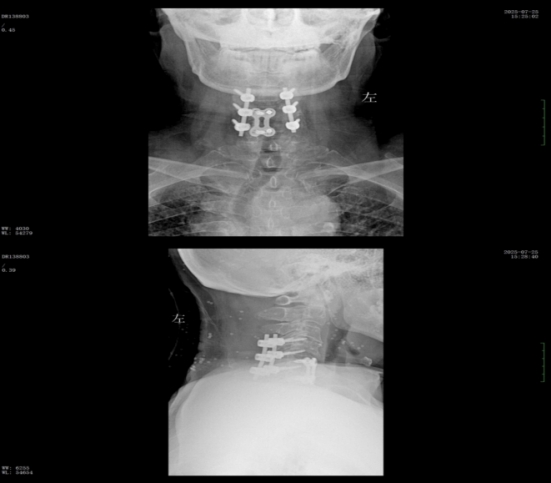

經(jīng)過精準(zhǔn)手術(shù)和術(shù)后系統(tǒng)的康復(fù)治療,患者神經(jīng)功能得到明顯恢復(fù),四肢肌力及感覺逐步改善,術(shù)后肌力達(dá)到IV級(jí)左右。復(fù)查X線顯示內(nèi)固定位置理想,患者非常滿意。出院之際,患者及家屬對(duì)衡陽市中心醫(yī)院的醫(yī)療技術(shù)、護(hù)理服務(wù)及醫(yī)聯(lián)體轉(zhuǎn)診效率均給予高度評(píng)價(jià)。

wps2.jpg

術(shù)后x線內(nèi)固定位置理想